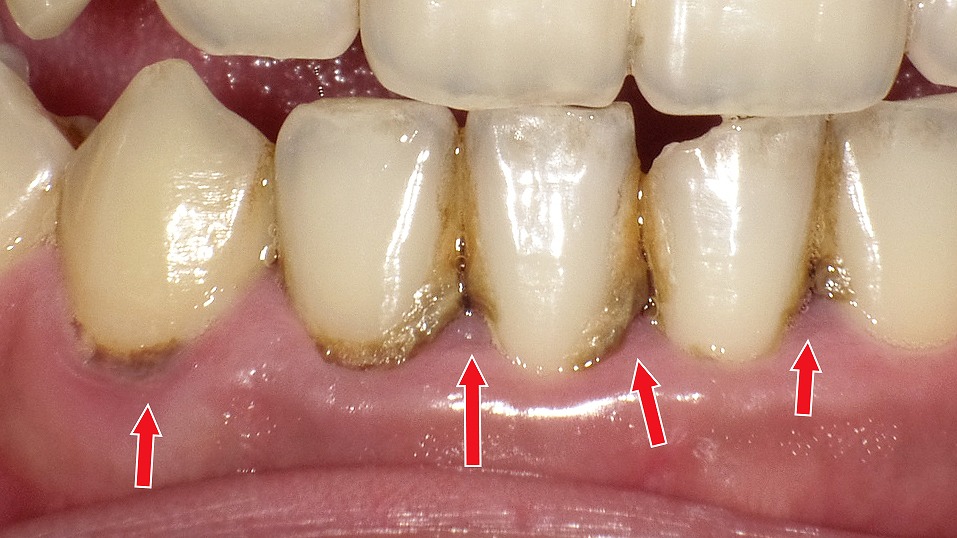

歯石の黒色化

歯の根元や歯と歯の間に付着した歯石が、唾液中の成分や細菌の代謝物、タバコのヤニなどと反応して黒く変色した状態を「縁下歯石(黒色歯石)」と呼びます。

黒色歯石は、通常の白っぽい歯石よりも硬くて強固に付着するため、日常のブラッシングでは取り除くことができません。

このタイプの歯石が見られる場合、

- 歯周病が進行しているサインであることが多い

- 歯肉の炎症や出血を引き起こしやすい

- 歯周ポケットの内部にまで及ぶことがある

といった特徴があります。

除去するには、歯科医院で行うスケーリングやルートプレーニングが必要です。黒色歯石を放置すると細菌の温床となり、歯周病が悪化する恐れがあるため、早めのケアが重要です。